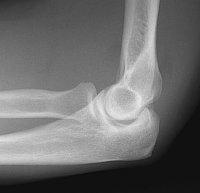

Visualization of a lipohemarthrosis in the elbow is joint is rare. It can only be seen radiographically on lateral views of the elbow with intraarticular fractures. It can be seen with CT, but this examination is not performed often in the acute setting. A more common finding in the acutely injured elbow is a displaced fat pad. This sign was first described in 1954. Often, subtle fractures of the radial head cannot be detected radiographically, but their presence can be inferred due to the presence of a joint effusion (blood) which on the lateral view of the elbow, displaces the anterior (coronoid) and posterior (olecranon) fat pads away from the joint. It is commonly believed that the presence of a displaced posterior fat pad is a more sensitive indicator of occult fracture than displacement of the anterior fat pad. Approximately 5 - 15 cc of fluid is required to displace these two fat pads so that they are radiographically detectable. The anterior fat pad should only be barely perceptible in the normal elbow. Case1: A 30 year old male fell while playing tennis. Image 1: The lateral radiograph of the elbow demonstrates the presence of abnormal anterior and posterior fat pads, due to the presence of blood within the joint from a nondisplaced radial head fracture. CLICK TO ENLARGE. Case 2: A 13 year old boy fell while playing soccer. Image 1: This lateral radiograph of the elbow demonstrates a true lipohemarthrosis of the elbow joint. Again, there is a crescent shaped region of low density anterior to the radial head. This corresponds to fat which has migrated from the marrow space to the joint space through an intraarticular fracture. The fracture itself is not visible. CLICK TO ENLARGE.